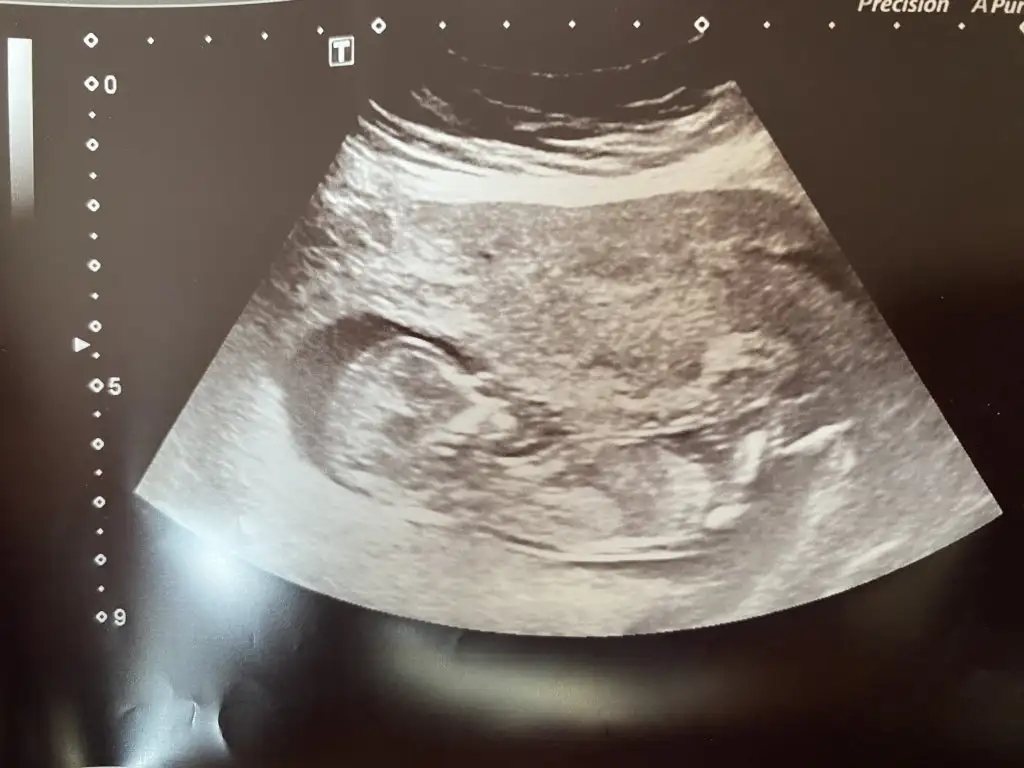

Bu da bacak arasıYüzde yüz milyon erkek besbelli canım benim oğlumun da böyleydi ultrason görüntüleri

Aynen bacak arasında nohuta benzer gözüküyor erkekte bende oğlumun ultrason görüntülerini bulup atayım inşaEllah bi ara canım karşılastırBu da bacak arası

Bacak arasında pipi var gibime geldiKız gibi